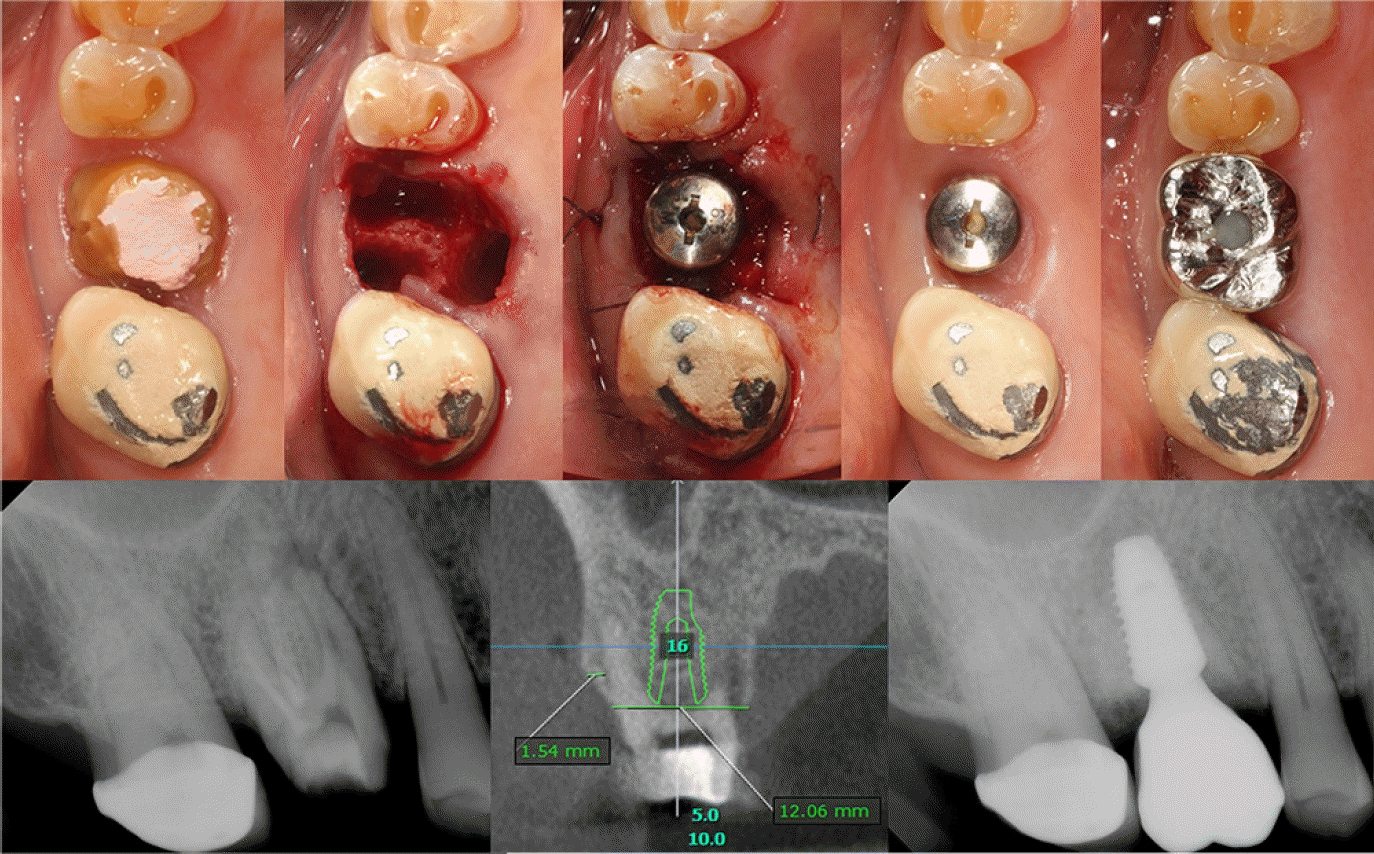

Case 1: Immediate implantation of #16i

A 67-year-old male, diagnosed with a cracked tooth, was referred for extraction and implant placement on the maxillary right first molar. A crack line and apical radiolucency lesion were observed at the mesiobuccal root on the periapical radiograph. The virtual planning was conducted with a computer software(OnDemand3D version 1.0, Cybermed Inc., Daejeon, South Korea) based on the conebeam-computed tomography(CBCT) taken before the surgery. Intact buccal wall was observed in the cross-sectional view, which allowed immediate implant placement. At the day of surgery, the maxillary right first molar was extracted and a dental implant fixture with sandblasted, large-grit and acid-etched(SLA) surface(Superline, Dentium, Suwon, South Korea), 5.0 x 10mm(diameter x length), was placed at the septal bone by free-hand surgery, followed by grafting of porcine-derived xenogeneic bone substitute(THE Graft, Purgo Biologics, South Korea) in the 3-mm circumferential gap defect. After applying a collagen sponge(Teruplug, Olympus Terumo Biomaterials, Tokyo, Japan) to secure the bone graft, HA(Healing abutment, Dentium) was connected to the fixture and then sutured with a resorbable 4-0 glyconate monofilament suture material(Monosyn®, B. Braun, Tuttlingen, Germany). The overall procedure is summarized in Figure 1.Case 2: Immediate implantation of #25i

Figure 1.

Clinical photographs and radiographs of Case 1 with commercial healing abutment (HA) connection after immediate implantation.